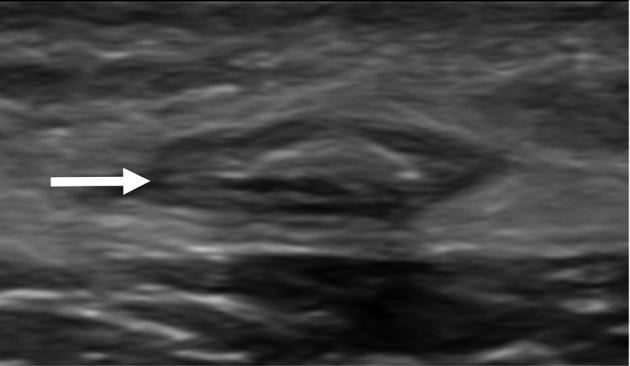

Klippel-Trénaunay syndrome is characterized by a persistent lateral embryonic vein. This so-called marginal vein has a large diameter causing venous stasis and venous hypertension because of the absence of valves along its entire length. The extensive diameter of the vein impedes successful treatment by sclerotherapy. Surgical removal is considered technically challenging for potential severe intraoperative blood loss due to the large perforators to the deep veins. Here we show that endovenous treatments (laser ablation, cyanoacrylate adhesive) might be feasible options in therapy for lateral embryonic veins.

克-特综合征的特征是存在持续的胚胎外侧静脉。这条所谓的边缘静脉直径较大,由于其全长无瓣膜,导致静脉淤滞和静脉高压。静脉直径过大阻碍了硬化疗法的成功治疗。由于通向深静脉的大穿支静脉,手术切除在技术上具有挑战性,可能会导致术中严重失血。在此我们表明,腔内治疗(激光消融、氰基丙烯酸酯粘合剂)可能是治疗胚胎外侧静脉的可行选择。